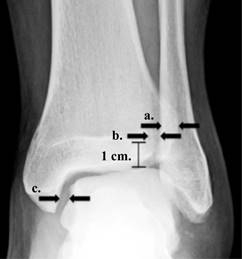

Se realizaron tres mediciones radiográficas, las cuales fueron: el espacio tibioperoneo (ETP), que es la distancia entre el borde medial del peroné y el borde lateral del tubérculo posterior de la tibia; la superposición tibioperonea (STP), que es la distancia entre el borde medial del peroné y el borde lateral del tubérculo anterior de la tibia; y el espacio astrágalo-tibial medial (EATM), que es la distancia entre el borde medial del astrágalo y el borde lateral del maléolo medial (Figura 3).

Figura 3: Proyección radiográfica anteroposterior de tobillo izquierdo que muestra las mediciones radiográficas utilizadas para lesión de la sindesmosis tibioperonea, incluyendo superposición tibioperonea (A), espacio tibioperoneo (B) y espacio tibio-astragalino medial (C)